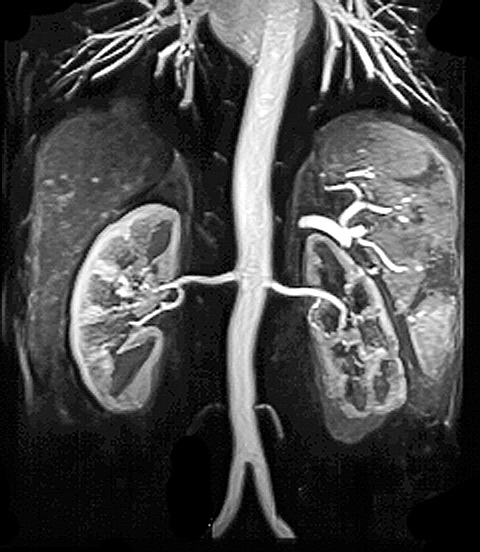

MR-angiografi af normal aorta og nyrearterier.